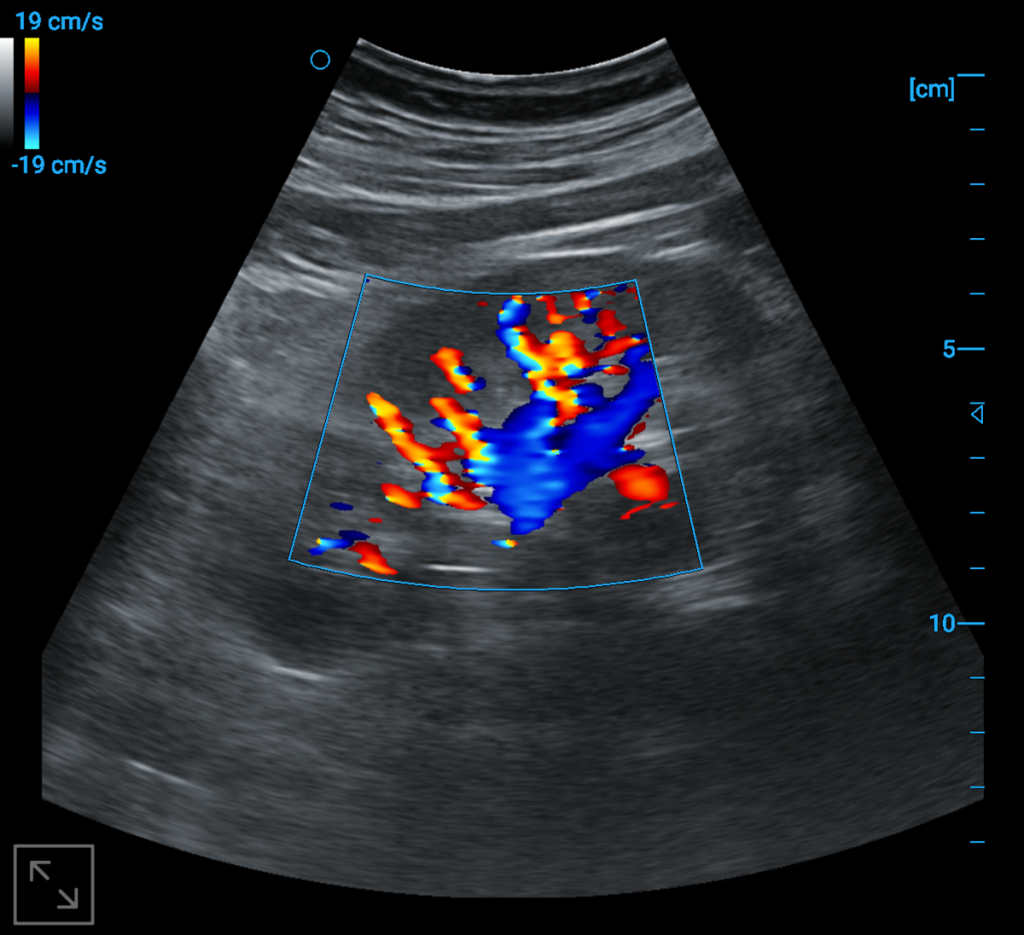

Kindey blood flow